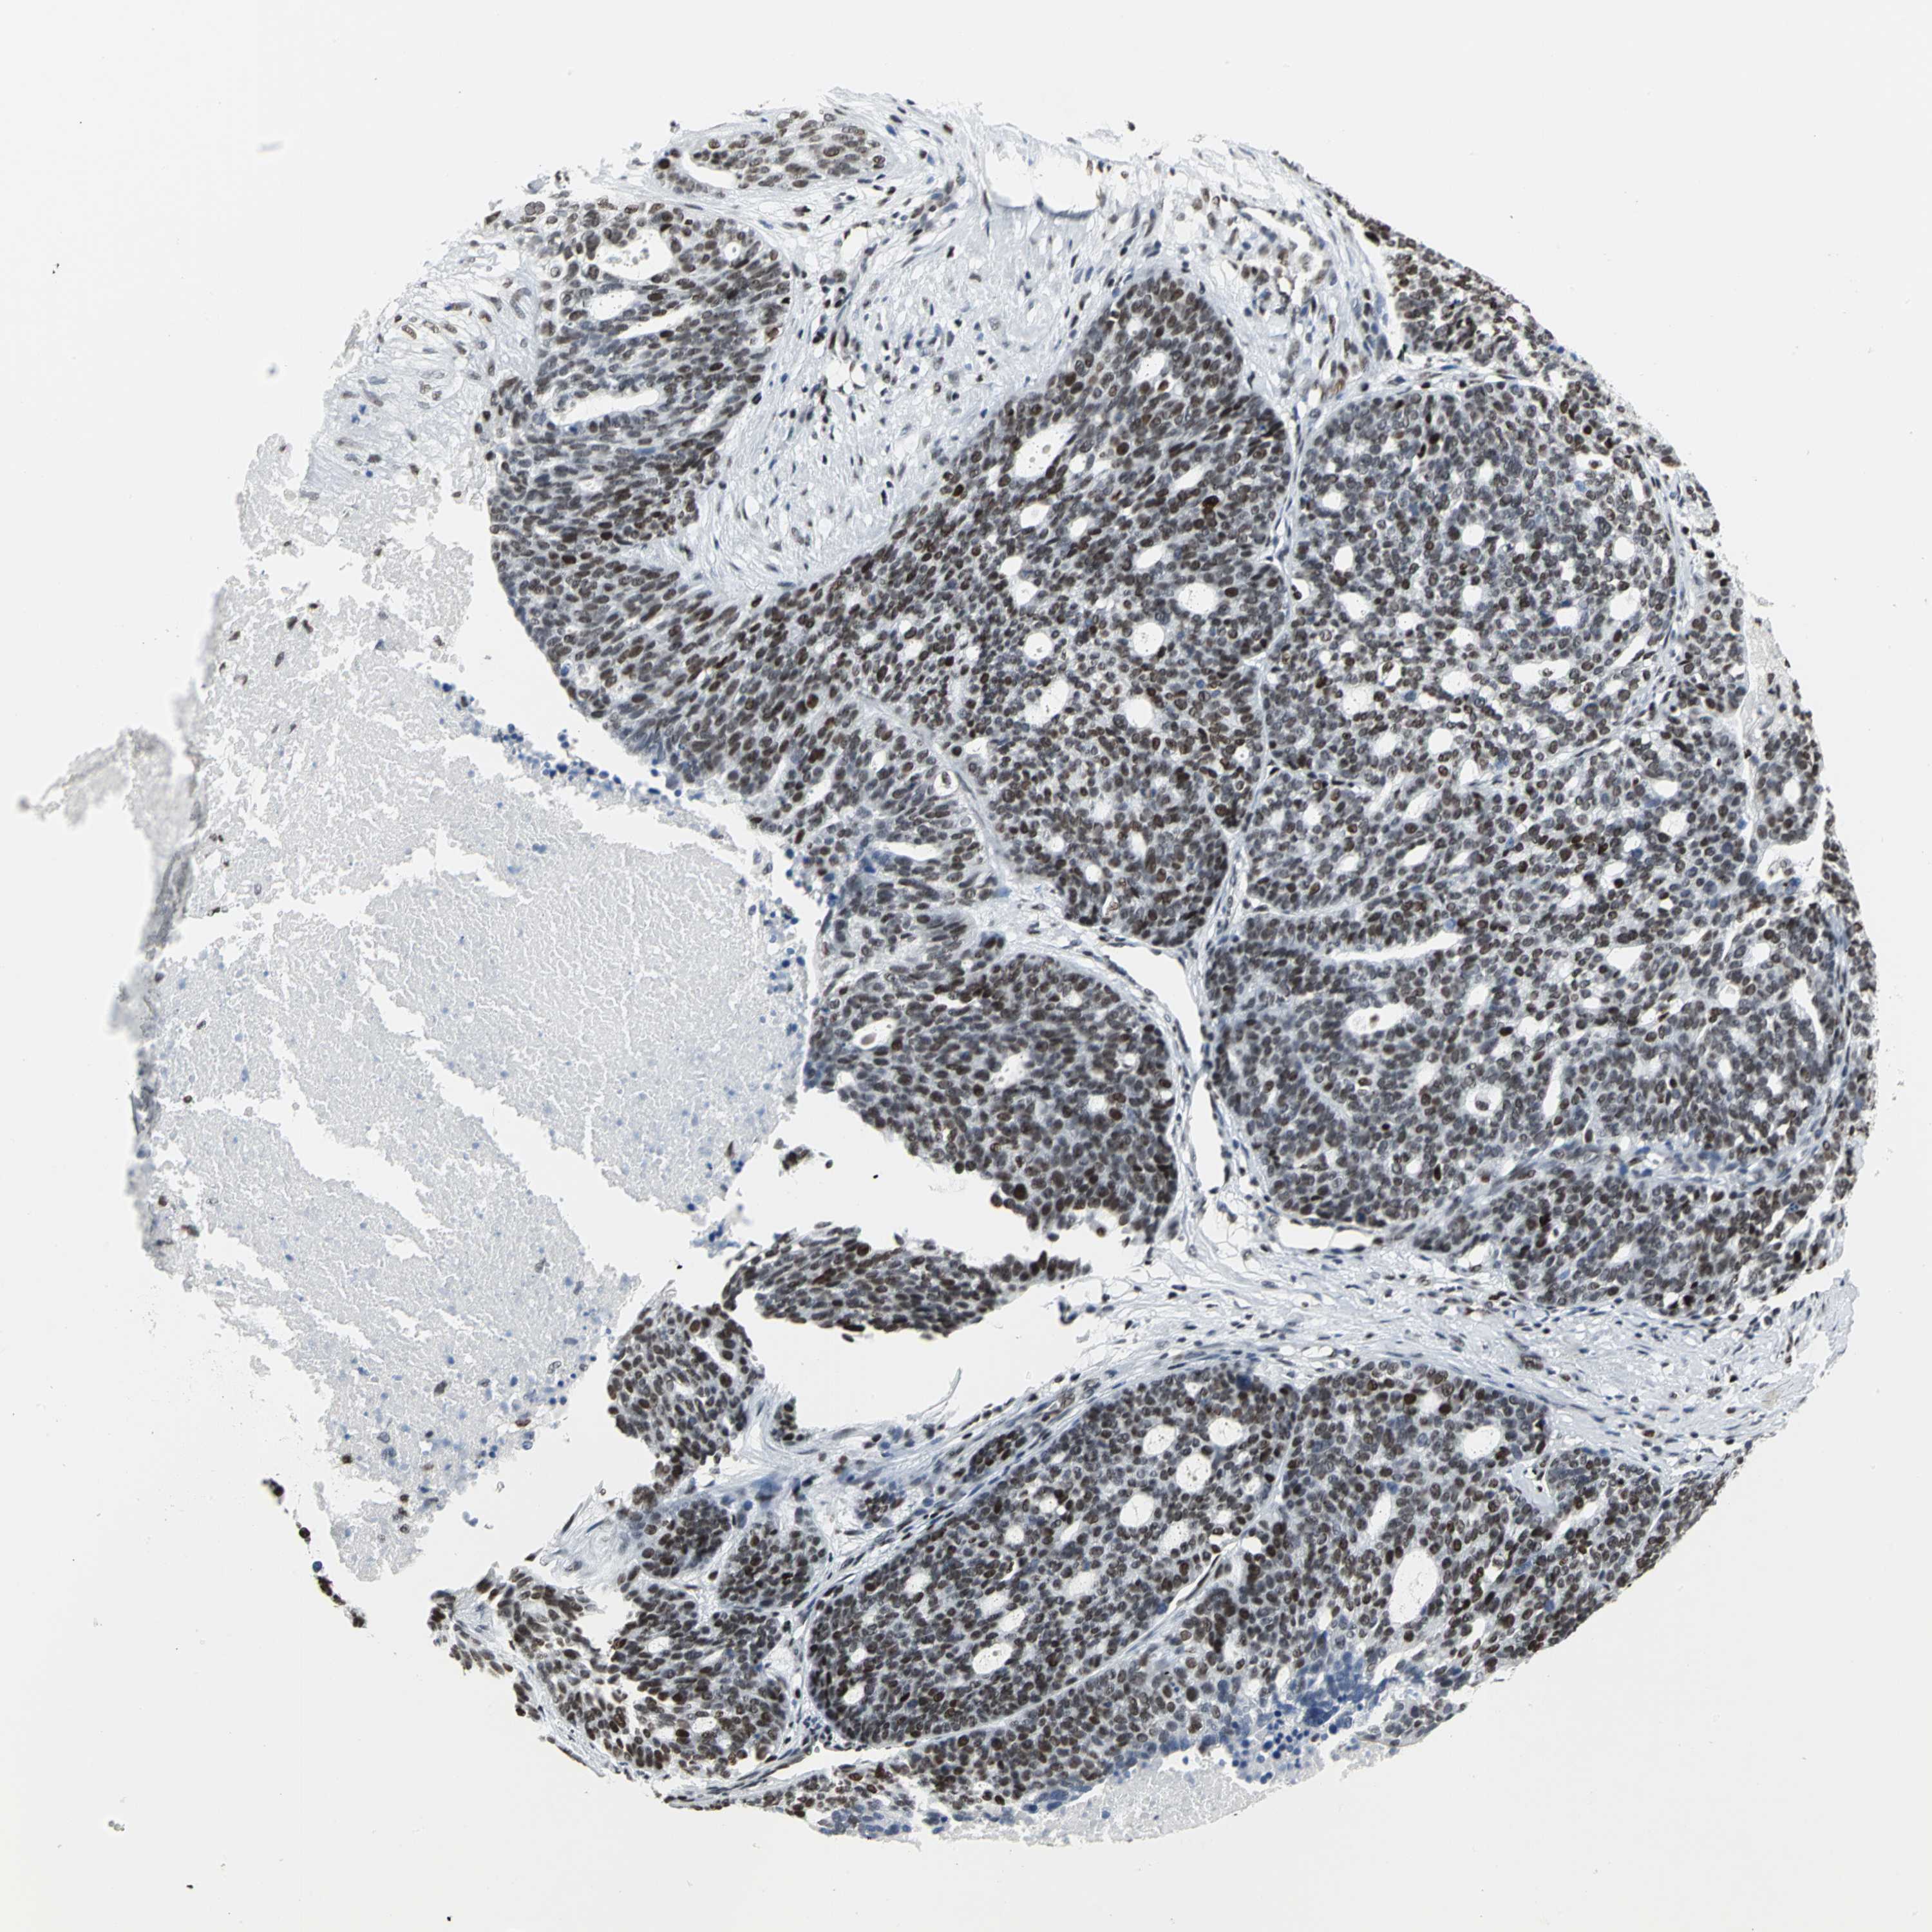

OVARIAN CANCER - Protein expressioni

A mouse-over function shows sample information and annotation data. Click on an image to view it in a full screen mode. Samples can be filtered based on level of antibody staining by selecting one or several of the following categories: high, medium, low and not detected. The assay and annotation is described here.

Note that samples used for immunohistochemistry by the Human Protein Atlas do not correspond to samples in the TCGA dataset.

Antibody stainingi

Antibody staining in the annotated cell types in the current human tissue is reported as not detected, low, medium, or high, based on conventional immunohistochemistry profiling in selected tissues. This score is based on the combination of the staining intensity and fraction of stained cells.

Each image is clickable and will lead to virtual microscopy that enables deeper exploration of all samples and also displays staining intensity scores, fraction scores and subcellular localization as well as patient and tissue information for each sample.

Antibody HPA004911

Staining

High

Medium

Low

Not detected

Intensity

Strong

Moderate

Weak

Negative

Quantity

>75%

75%-25%

<25%

None

Location

Nuclear

Cytoplasmic/membranous

Cytoplasmic/membranous,nuclear

Cystadenocarcinoma, mucinous, NOS